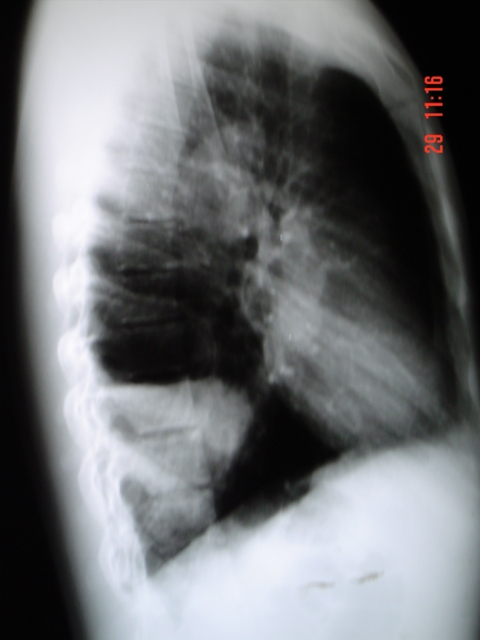

- <div style=fiogf49gjkf0dFig.1-2. Radiografía Posteroanterior y Lateral dónde se evidencia imagen radioopaca de bordes bien definidos con nivel líquido en su interior localizada en base posterior derecha.">

Fig.1-2. Radiografía Posteroanterior y Lateral dónde se evidencia imagen radioopaca de bordes bien definidos con nivel líquido en su interior localizada en base posterior derecha.